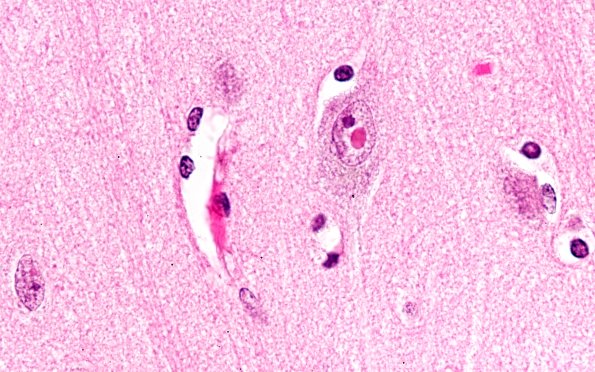

Washington University Experience | NEURODEGENERATION | Neuronal Nuclear Inclusion Disease (NIID) | 3A4 NIID (AANP DSS 2005-3) cortex cerebral 100X 1

This high magnification, oil immersion image shows the inclusion and an adjacent nucleolus. (H&E)